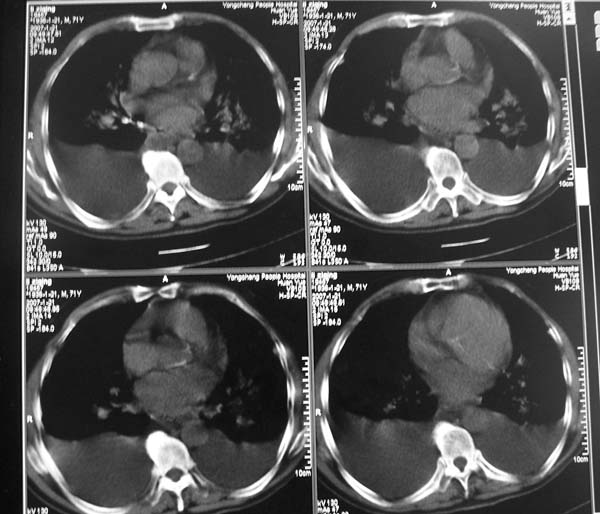

以下是引用zyx168在2007-1-21 17:08:00的发言:[br]男,71岁,咳嗽、胸闷10天余,咯血1天。[br]两肺大片状密度均匀影,充气支气管征象明显,左房增大,双侧胸腔内新月形液性密度影。[br]考虑:1,心源性肺水肿伴双侧胸腔中等量积液;[br] 2,两肺肺炎?